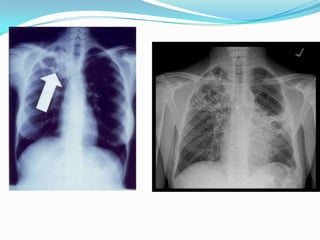

TBC: Diagnóstico: Rx Tórax

 Manifestaciones variadas e inespecíficas.

TBC Primaria:

 Linfoadenopatías.

 Opacidades

parenquimatosas,

tanto del espacio aéreo

como del intersticio,

siendo la

consolidación del

espacio aéreo el patrón

radiológico más

común, acompañado

TBC: Diagnóstico:Rx Tórax

Compromete con

mayor frecuencia

segmento apical o

posterior de lóbulos

superiores.

Otras manifestaciones:

1) Enfermedad

traqueobronquial:

Atelectasias o

hiperinsuflación

secundaria.

2) Enfermedad pleural:

derrame de tamaño

 TBC Postprimaria:

 Distintivo: Predilección por los

lóbulos superiores, ausencia

linfodenopatías y propensión a

excavación.

Consolidación del espacio aéreo:

patrón común.

 La excavación es también

una característica

importante de la

tuberculosis post-primaria.

Cavernas

 Mezcla de patrones radiográficos:

opacidades lineales, reticulares y

nodulares.

La resolución de las anormalidades radiológicas es lenta. La

radiografía de tórax no es el mejor método de vigilar la

respuesta al tto. ATB.